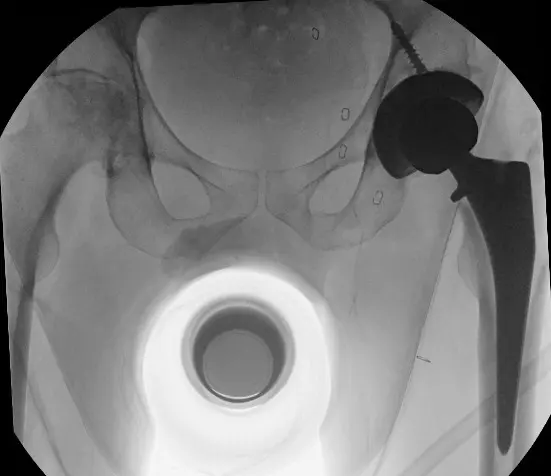

Total Hip Replacement – Before and After Images

Total Knee Arthroplasty